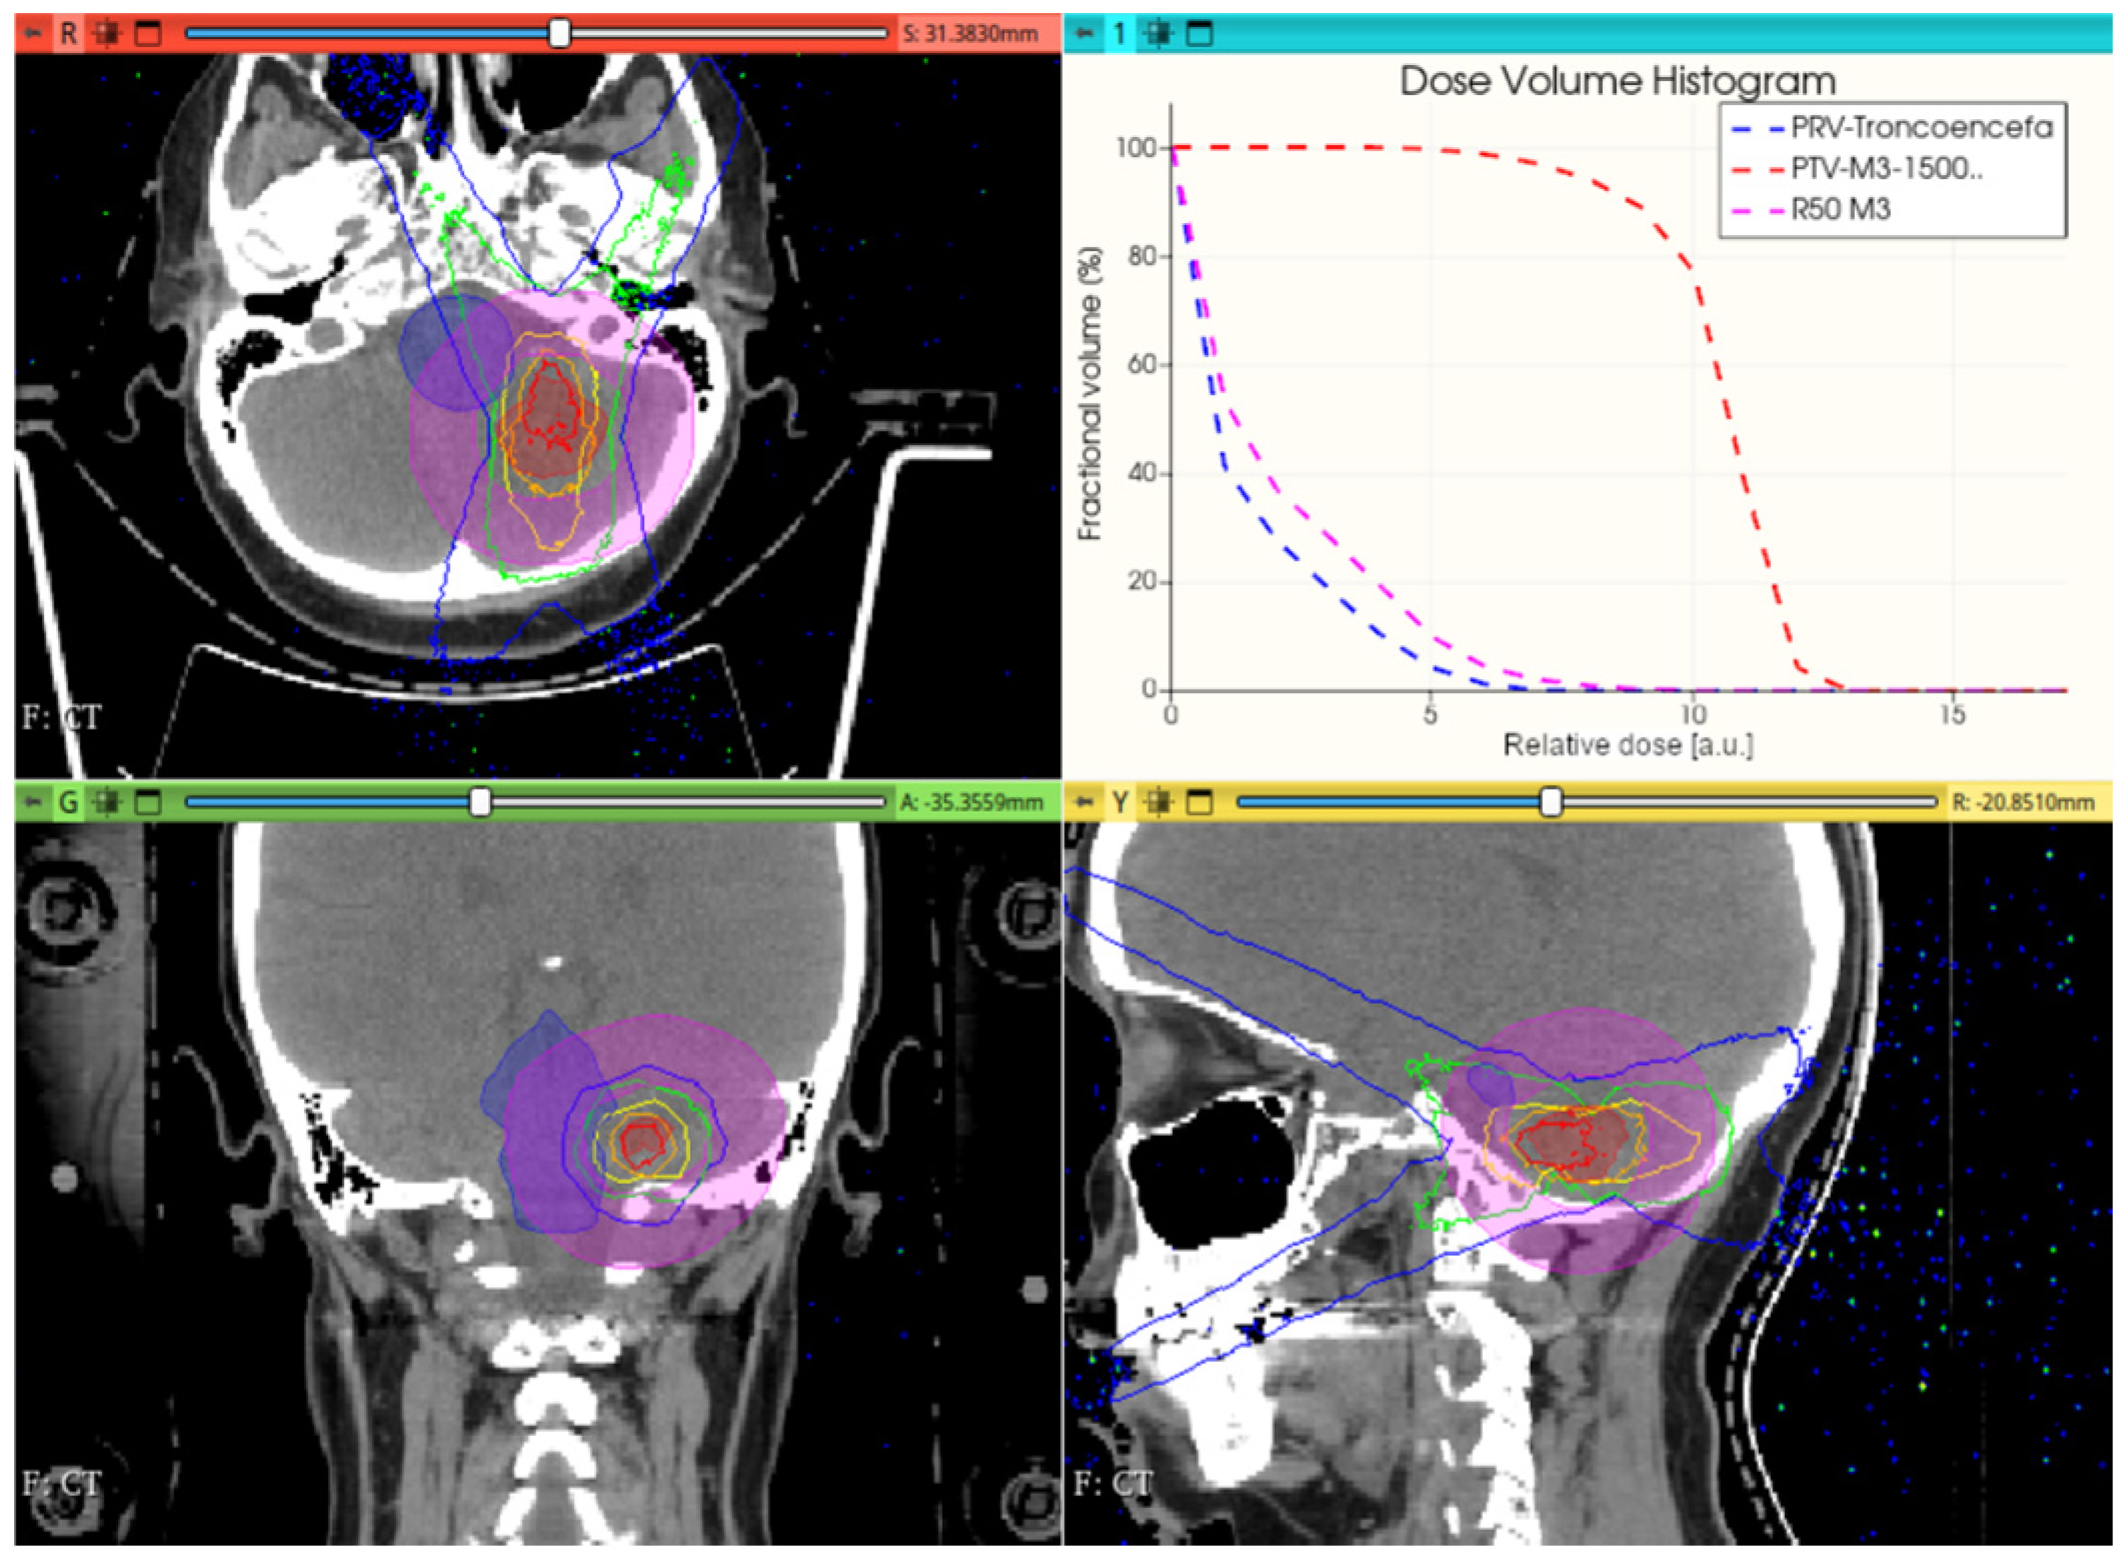

3.3.1. Preliminary CONVERAY Dosimetry Performance for Intracranial Irradiations